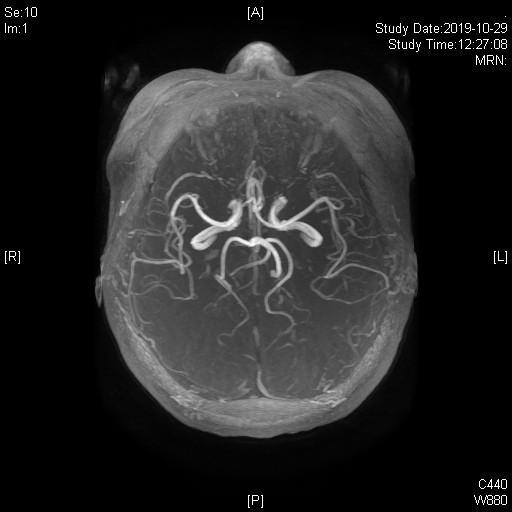

术前3D-TOF序列见左侧小脑前下动脉AICA从基底动脉发出,并弯曲成袢。

TOF序列及FIESTA序列见AICA向桥脑延髓沟方向弯曲,并与REZ区关系密切。